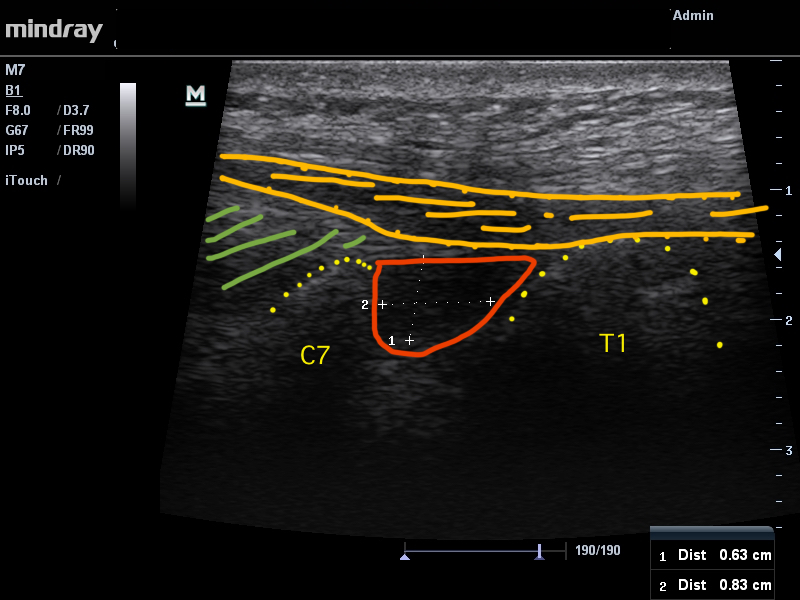

L’examen échographique (FIGURES 2 et 3) a permis de mettre en évidence la présence d’une bursite interépineuse. Il s’agit de l’inflammation d’une petite structure, jouant le rôle de « coussin » située entre les apophyses épineuses. Cette bourse n’est retrouvée que chez 50% de la population. La bursite peut être retrouvée dans un contexte rhumatismal particulier intéressant les personnes agées. Dans le cas de notre patiente, nous avons émis l’hypothèse que cette petite bourse ait pu s’enflammer du fait des contraintes mécaniques imposées sur son cou lors de l’intervention chirurgicale.

FIGURE 3. La zone orange représentant le supraspinous ligament (discrètement épaissi au niveau de la zone douloureuse). La zone verte le nuchal ligament. Les pointillés jaunes la corticales des apophyses épineuses. La zone rouge la bursite interépineuse. FacebookTwitterEmailPartager